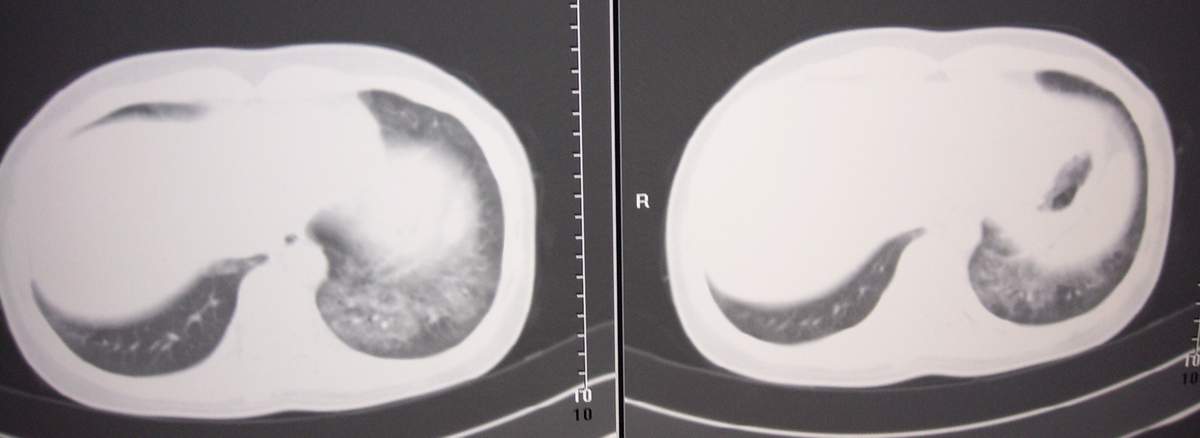

标题: CT7371:[讨论]肺部病变!

女,咳嗽、气喘2月余。

两肺弥漫性病变,考虑:1。肺水肿。2。肺蛋白沉积症。

双肺弥漫性病变, 冠状重建肺血管增粗,建议继续上传详细临床资料,x线片

双肺弥漫性病变是肺部疾病诊断的难点和重点,需要很好的结合临床,如发烧不?心功能如何?免疫功能如何?另外我们影像科也应进一步把工作做细,如本病例应行高分辨扫描。

双肺弥漫磨玻璃样影,边界不清,似蝶翼征。肺纹理增多。

考虑:肺泡蛋白沉积症。建议临床进一步检查。